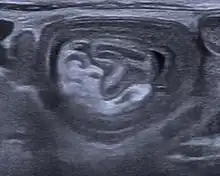

An intussusception is often suspected based on history and physical exam, including observation of Dance's sign. A digital rectal examination is particularly helpful in children, as part of the intussusceptum may be felt by the finger. A definite diagnosis often requires confirmation by diagnostic imaging modalities. Ultrasound is the imaging modality of choice for diagnosis and exclusion of intussusception, due to its high accuracy and lack of radiation. The appearance of target sign (also called "doughnut sign" on a sonograph, usually around 3 cm in diameter, confirms the diagnosis. The image seen on transverse sonography or computed tomography is that of a doughnut shape, created by the hyperechoic central core of bowel and mesentery surrounded by the hypoechoic outer edematous bowel.[10] In longitudinal imaging, intussusception resembles a sandwich.[10] It is also called "pseudokidney" sign because hyperechoic tubular centre is covered by a hypoechoic rim producing a kidney-like appearance.[11]